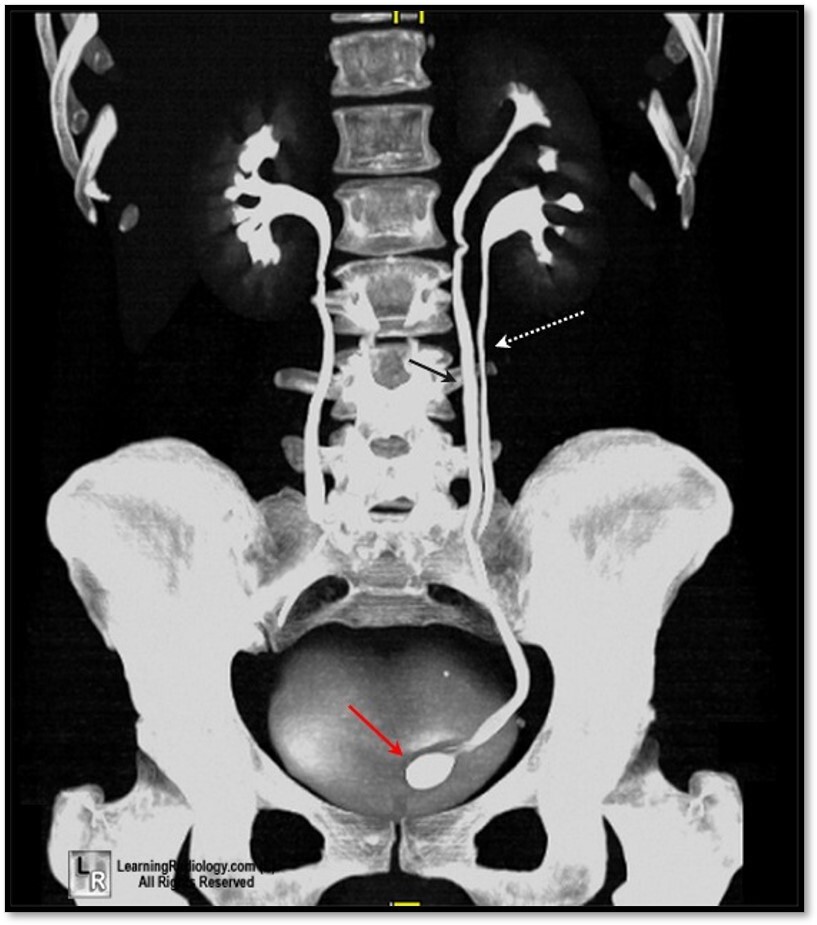

31

What is the dotted and solid arrow pointing to?

Dotted arrow: Kidney stone (urolith) Solid arrow: Phleboliths